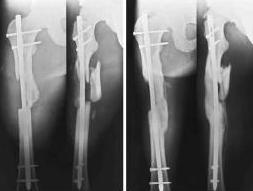

жесткой фиксации")и картинки в ряде классических руководств (вложеннный рисунок)

А вот если дать раннюю нагрузку на мыщелковые переломы бедра, может случится беда.